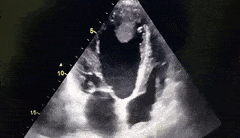

Identify the cardiac pathology demonstrated in the image.

Right atrial myxoma

Mitral stenosis

Tricuspid endocarditis/vegetation

Tricuspid stenosis